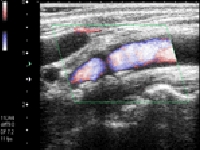

腹部の検査

オリンパスの最新鋭内視鏡システム(EVIS LUCERA ELITE)での胃内視鏡、大腸内視鏡、経鼻胃内視鏡(鼻から挿入する内視鏡)による観察(NBI観察も可能)と早期癌・ポリープ切除などの処置を行っています。また全例コンピューターでの録画を行い、検査後に録画映像にて詳細な説明を行います。さらにコンピューターファイリングシステムによる迅速な診断を行っております。